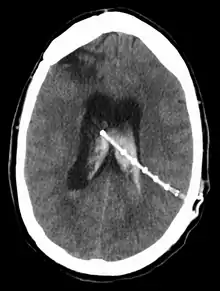

النزف داخل البطيني

يمكن أن يحدث النزف داخل البطيني في أي وقت أثناء أو بعد إدخال أو إرجاع التحويلة. ييمكن أن يسبب النزيف ضعف في وظيفة التحويلة التي يمكن أن تؤدي إلى قصور عصبي حاد. وقد أظهرت الدراسات أن النزف داخل البطيني يمكن أن يحدث في ما يقرب من 31٪ من تكرارات التحويلات.[24]